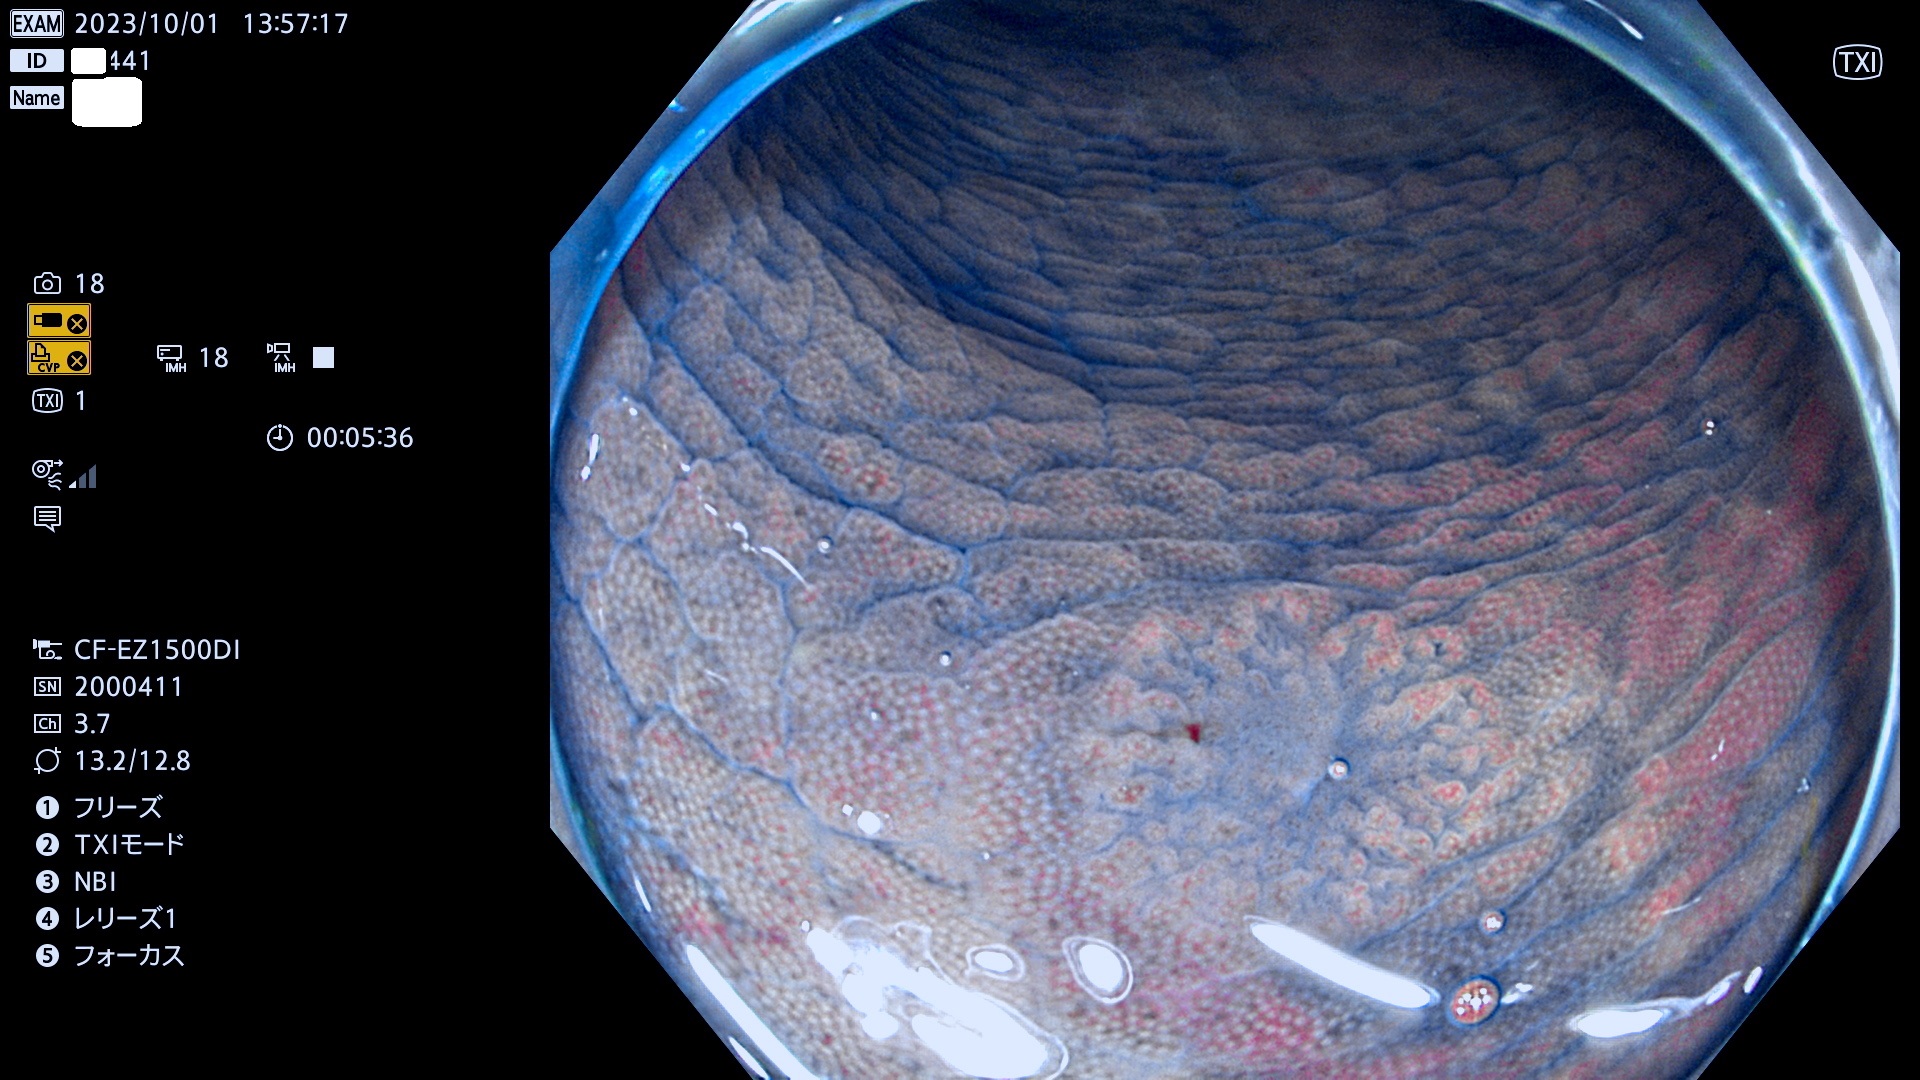

表面型腺腫(Flat Adenoma)の中で、完全に平坦な物をUb、陥凹している物をUcと呼びます。平坦隆起型(Ua)よりも、発見が難しく危険な病変です。このタイプは「内視鏡後・大腸癌の重要犯人」であり、この発見率は「腺腫発見率」よりも、重要な意味があります。

毎週の検査(木・金・土・日)に発見されたUb、Uc型・腺腫を、その週の日曜の夜にUPし1週間、提示します。

抽出の対象期間 2023年9月28日(木)〜10月1(日)の4日間(48件の検査)8件